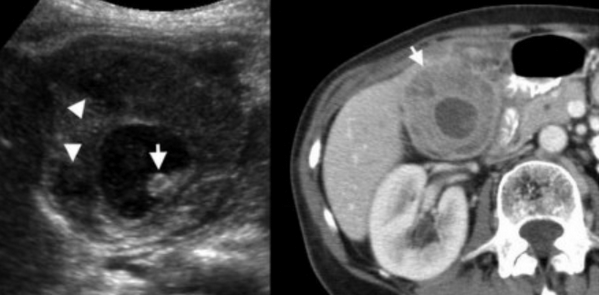

(Левый) При КТ с контрастным усилением у пациента с острым бескаменным холециститом визуализируются растянутый желчный пузырь с утолщенной стенкой, скопление перипузырной жидкости и воспаление перипузырной жировой клетчатки. Обратите внимание на слабое контрастирование стенки в области дна желчного пузыря.

(Правый) На поперечном УЗ срезе у пациента с бескаменным холециститом определяется сладж, утолщение стенки и чрескожный холецистостомический дренаж. Также видно скопление перипузырной жидкости.